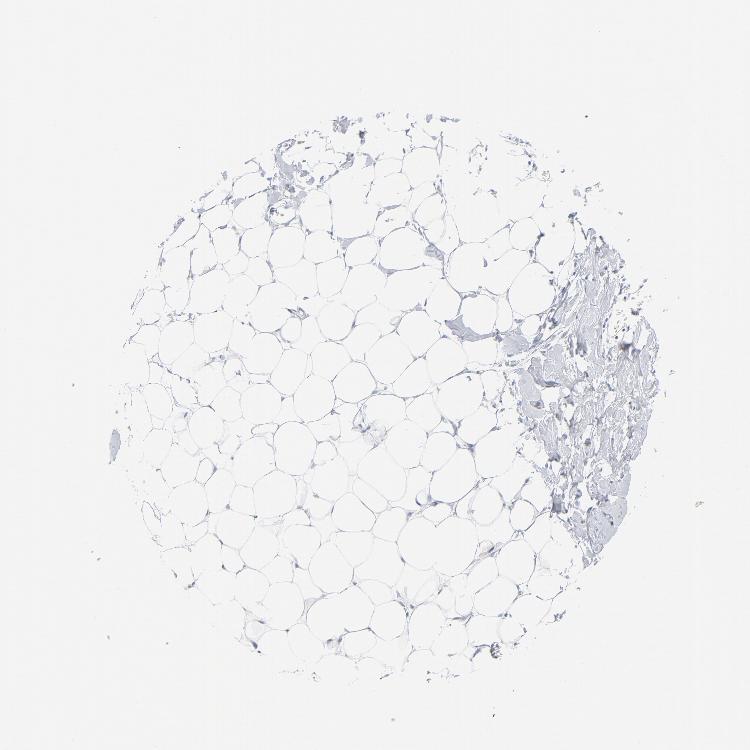

BREAST - Antibody stainingi

Antibody staining in the annotated cell types in the current human tissue is reported as not detected, low, medium, or high, based on conventional immunohistochemistry profiling in selected tissues. This score is based on the combination of the staining intensity and fraction of stained cells.

Each image is clickable and will lead to virtual microscopy that enables deeper exploration of all samples and also displays staining intensity scores, fraction scores and subcellular localization as well as patient and tissue information for each sample.

Antibody HPA003418Antibody CAB000376

Adipocytes Not detectedNot detected

Glandular cells Not detectedNot detected

Myoepithelial cells Not detectedNot detected